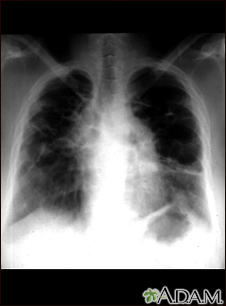

Sarcoid, stage IV - chest x-ray